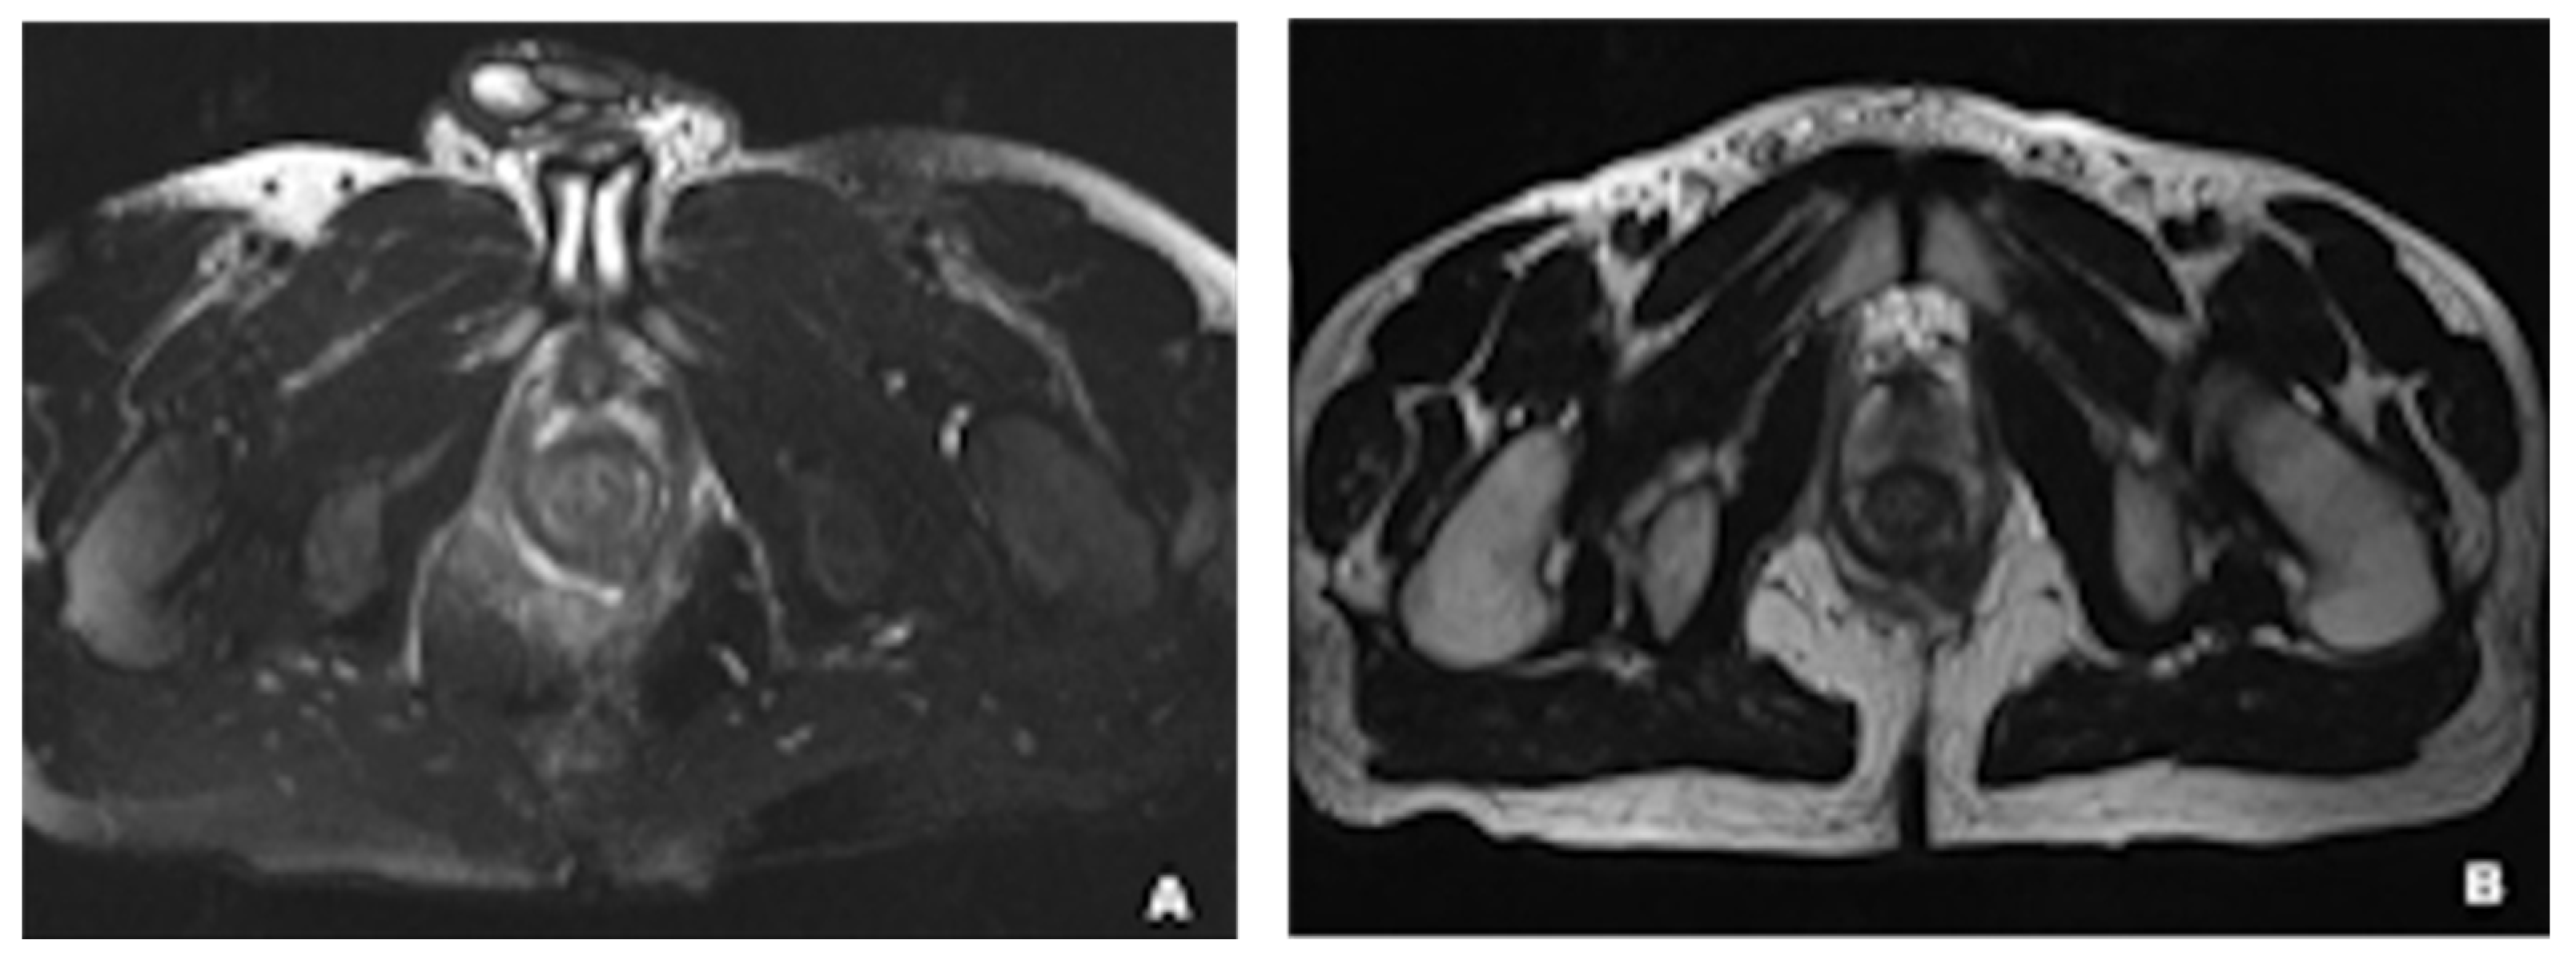

- Gallego, J.C.; Echarri, A. Role of magnetic resonance imaging in the management of perianal Crohn’s disease. Insights Imaging 2018, 9, 47–58. [Google Scholar] [CrossRef]

- Balcı, S.; Onur, M.R.; Karaosmanoğlu, A.D.; Karçaaltıncaba, M.; Akata, D.; Konan, A.; Özmen, M.N. MRI evaluation of anal and perianal diseases. Diagn. Interv. Radiol. 2019, 25, 21–27. [Google Scholar] [CrossRef]

- Reginelli, A.; Vacca, G.; Giovine, S.; Izzo, A.; Agostini, A.; Belfiore, M.P.; Cellina, M.; Floridi, C.; Borgheresi, A.; Palumbo, P.; et al. MRI of perianal fistulas in Crohn’s disease. Acta Bio-Med. Atenei Parm. 2020, 91, 27–33. [Google Scholar] [CrossRef]